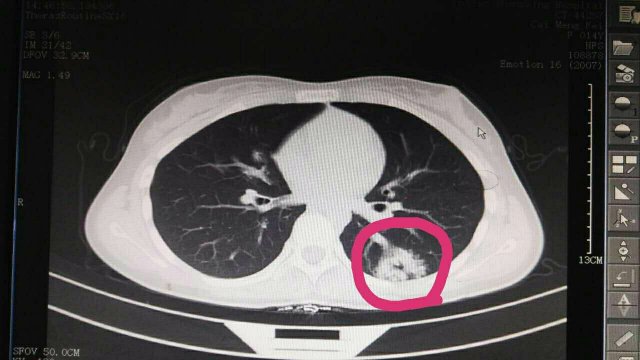

蔡**,女,14歲因“反覆頭暈3年余”,求診莆田及莆田各三級(jí)醫(yī)院,做過(guò)很多輔助檢查,均未確診,于2017-2-26日就診我院門(mén)診,接診是我院兒科林富醫(yī)師,經(jīng)過(guò)認(rèn)真仔細(xì)查體,發(fā)現(xiàn)患兒左側(cè)肩胛骨可聞及Ⅱ-Ⅲ/Ⅵ級(jí)收縮期雜音,為明確診斷,即刻請(qǐng)我院莊姞副主任醫(yī)師(原莆田市Di一醫(yī)院NICU主任)會(huì)診,查胸部CT發(fā)現(xiàn)左肺下葉背段血管畸形。莊姞副主任醫(yī)師告訴我們,部分型肺血管畸形如果不認(rèn)真查體是很難查體的到,年輕醫(yī)師能如此仔細(xì)查體,確診多家醫(yī)院未確診的疾病,不得不對(duì)林醫(yī)生豎起大拇指,通過(guò)此次經(jīng)歷,可見(jiàn)臨床醫(yī)生必須熟練掌握臨床三基的重要性。